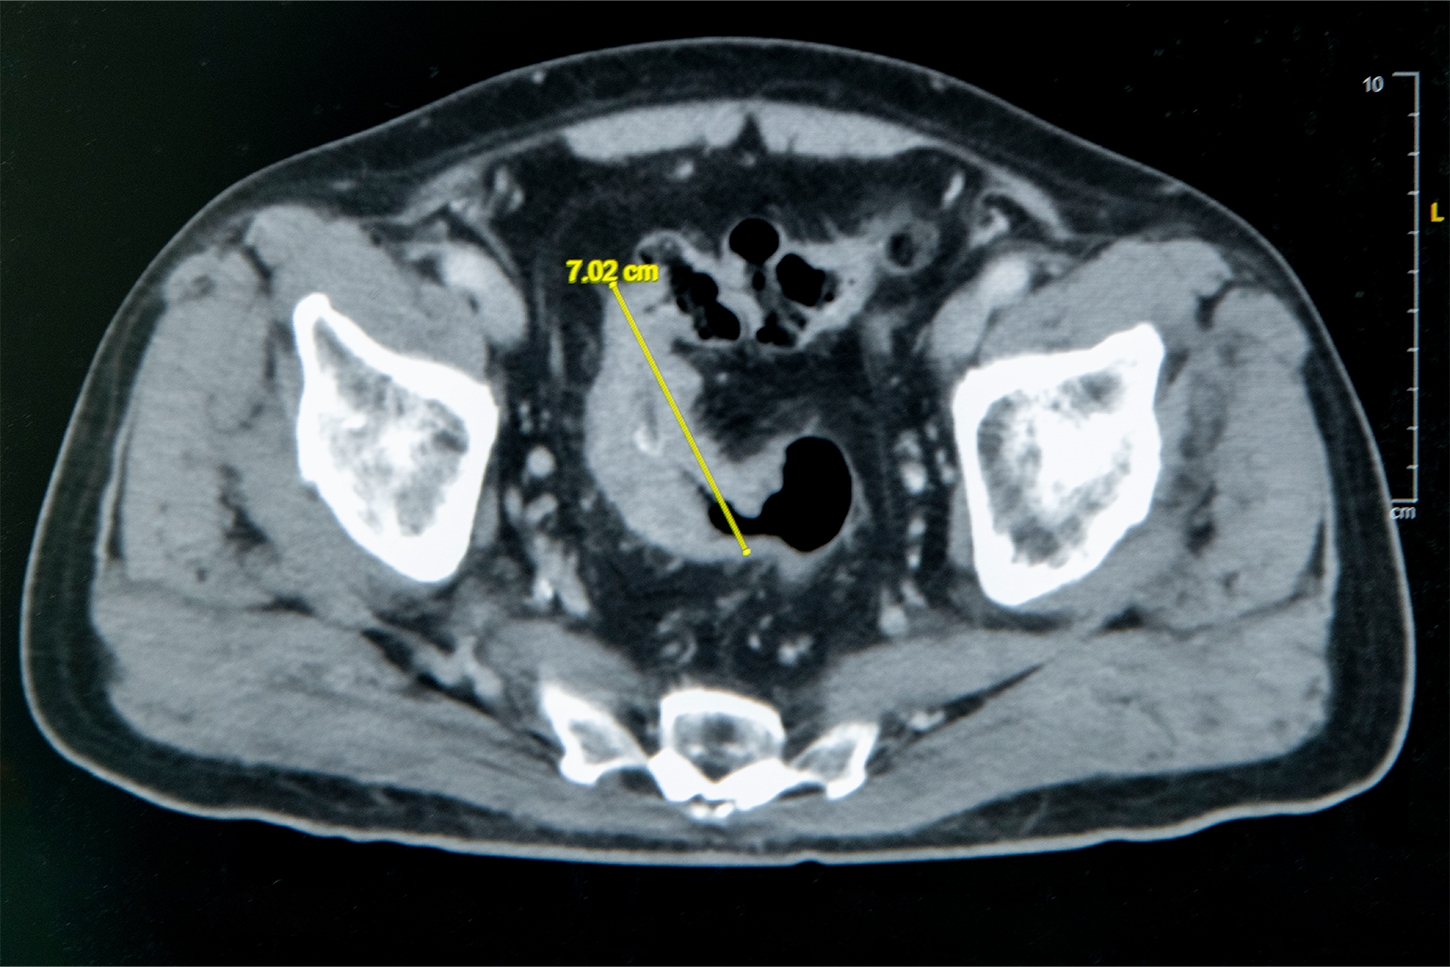

雲林七旬翁便秘竟是7 公分大腸癌 彰基單孔達文西SP手術助順利除癌

大腸直腸外科主任張譽耀醫師表示,老翁罹患乙狀結腸癌,腫瘤約7公分造成腸子幾乎完全阻塞,也導致老翁一進食就會肚子又脹又痛;術前因為不敢進食,老翁體重下降、營養不足,也可能造成傷口癒合不良。老翁的手術其實會有兩個傷口,一個是肚子上的傷口、一個腸子的傷口,若腸子傷口癒合不良會造成腸吻合滲漏,到時就必須做人工肛門了!所幸經過提早住院,透過靜脈營養針先建立營養,讓病人強健身體後才手術,術後傷口果然順利癒合。手術順利完成,老翁術後恢復良好,疼痛程度遠低於預期,他開心表示:「沒想到這麼快就能下床,真的很感謝醫師。」